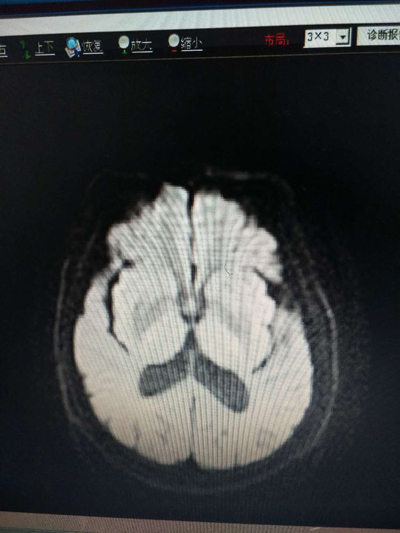

第二天复查头颅CT未见出血及梗死灶